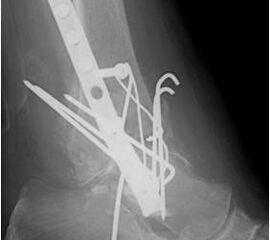

• Revision einer gescheiterten Fusion des OSG/ USG (Abbildung 3, Abbildung 4).